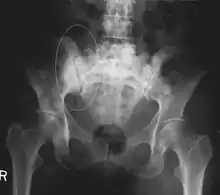

العظام هي أكثر ثالث مكان يصاب بالنقيلات السرطانية بعد الرئة والكبد. وفي الوقت نفسة يستطيع اي ورم سرطاني ان يكون نقيلة بالعظام حيث ان البيئة الدقيقة لنخاع العظام تميل إلى تفضيل انواع معينه من الأورام السرطانية تتضمنسرطانات البروستاتا وسرطان الثدي وسرطان الرئه. خاصة سرطان البروستاتا والذي لا يستطيع تكوين نقيلة سرطانيه الا في العظام. واشهرالأماكن لانتشار تلك الأورام في العظام هي العمود الفقري وعظمة الحوض والجزء العلوي من عظمة الفخذ.[1][2][3][4][5]